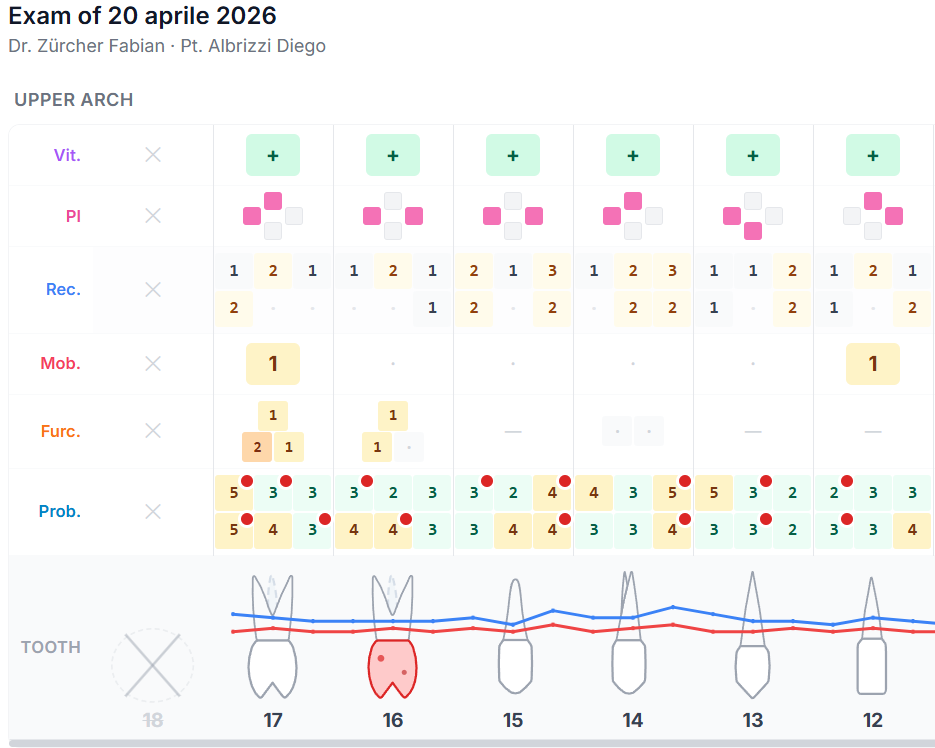

Parodontogramma completo.